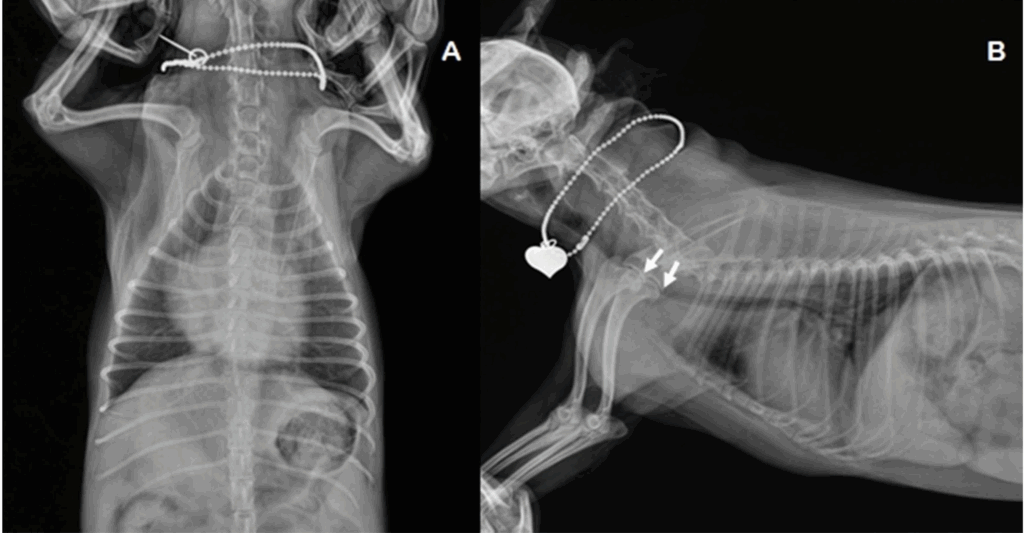

Fig 1. 증례 1의 흉부 방사선 사진입니다.

A: 배등 방향 촬영에서 특히 우심방을 중심으로 경도의 심장비대가 관찰되었습니다.

B: 우측 측면 촬영에서 심장 전방 허리(waist) 소실, 대동맥 근부 확장, 심장 비대, 기관의 등쪽 변위 및 흉부 기관의 중등도 허탈(흰색 화살표)이 관찰되었습니다.

( Thoracic radiography of the case 1. A: Ventrodorsal projection of radiography showed mild cardiomegaly especially with right chamber. B: Right lateral projection of radiography showed loss of cranial waist, dilation of aortic root, cardiac enlargement, dorsal displacement of trachea and moderate collapse of thoracic trachea (white arrows).)